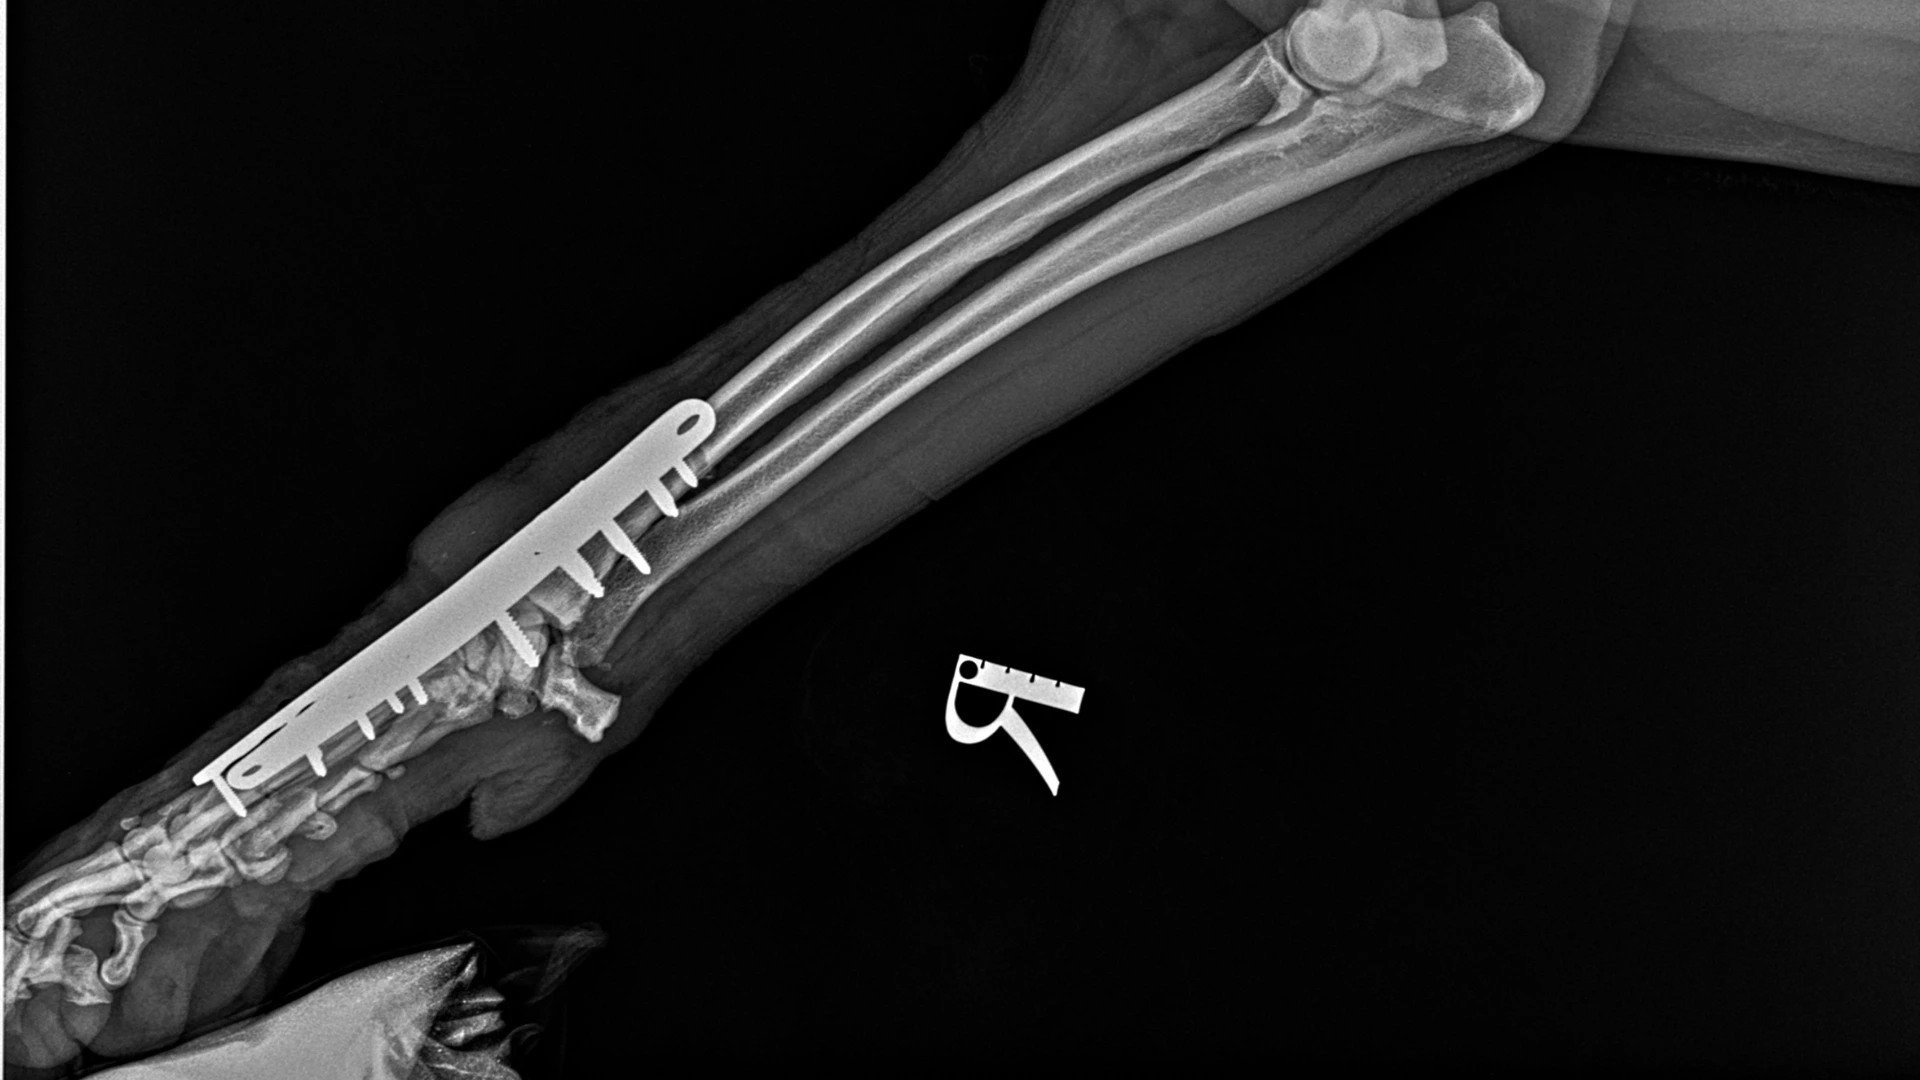

The surgical team prepared Max's joint for fusion, removing damaged cartilage and packing the joint with bone graph material to act as a supportive scaffold as new bone grows. A specially designed metal plate was then carefully positioned to hold everything in alignment as the bones fused together.

Surgery, even when performed by experienced veterinary surgeons, sometimes presents unexpected challenges. With Max's bones already weakened from his chronic disease, this meant that as the team tightened the screws to compress the joint and hold everything firmly in place, one of the bones in Max's paw (the third metacarpal bone) cracked through the screw hole.

This moment is where surgical experience and adaptability become crucial. The team reassessed, making the decision to reposition the plate to better support the cracked bone. A second, smaller plate was also added for additional support. This second plate acted like a splint, running along the neighbouring bone and providing extra stability to protect the crack while it healed.